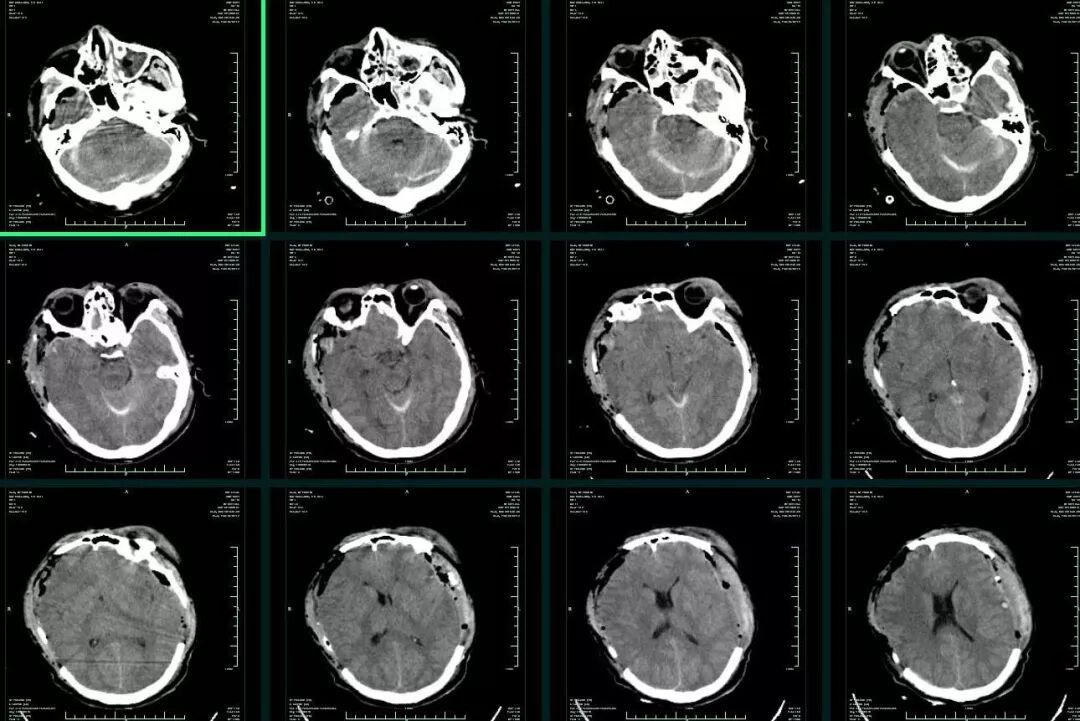

入院时患者深昏迷,GCS6分,左侧瞳孔0.5cm,右侧瞳孔0.3cm,对光反射均消失。急诊头颅CT提示:“左侧额颞顶部急性硬膜外血肿,脑疝(图1)”,急诊行左侧颅内血肿清除+去骨瓣减压术,术后即刻头颅CT复查提示:“右侧额颞叶急性硬膜下血肿”(图2),再次开颅行右侧颅内血肿清除+去骨瓣减压术。术后转ICU科呼吸支持治疗。术后再次复查CT,见血肿已清除,无硬膜下积液,中线基本居中(图3)。术后5天患者病情好转,GCS8分,双侧瞳孔0.3cm,对光反射迟钝,转回神经外科监护病房。

图3. 双侧血肿清除+去骨瓣减压术后次日CT复查,无明显硬膜下积液。